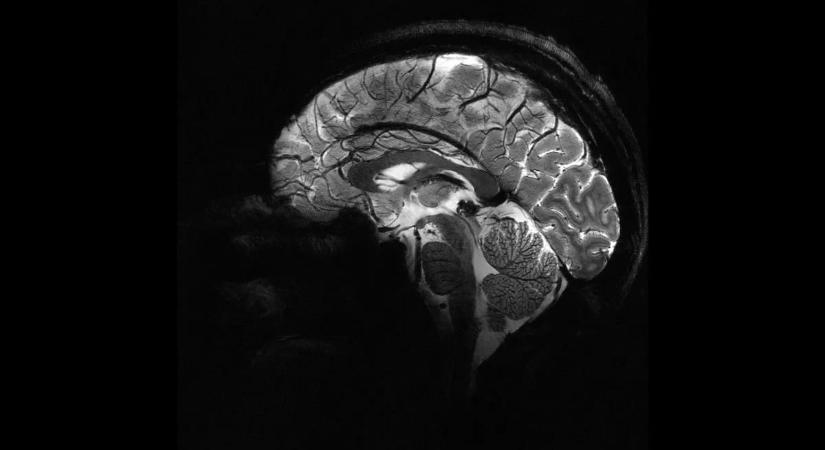

Amerikai kutatók szerint az ember belső cirkadián ritmusának óriási szerepe lehet abban, hogy megnő az Alzheimer-kór kialakulásának kockázata.